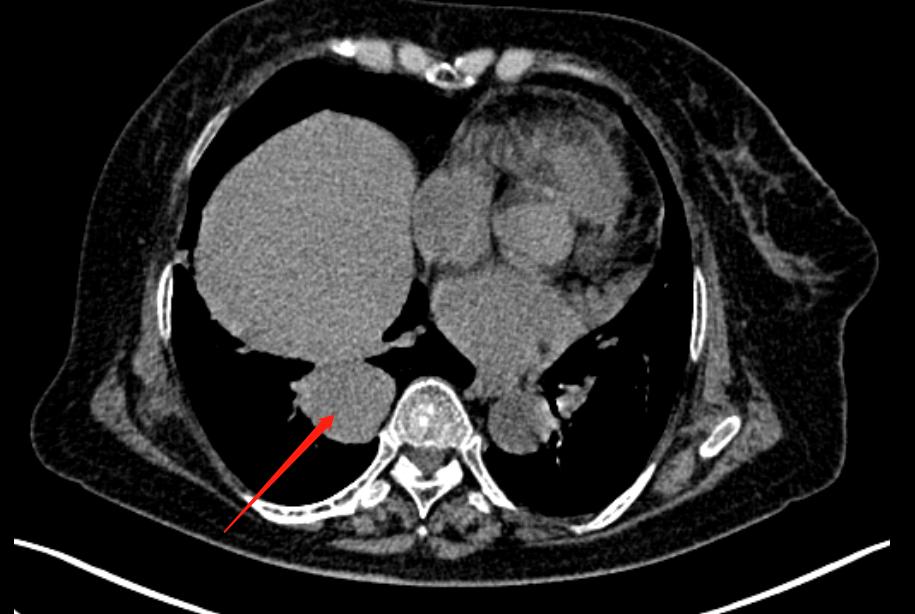

2022年6月20日上班遇到的病例(3):肺单发大转移瘤

女性 78岁 胸闷1年余,近期加重。

实性软组织结节,边界光整

病灶最大径超过4cm

纵隔窗提示为软组织密度

分析:实性软组织病变,之前分析得比较少,多发边界光整的实性小结节,以外周带分布的,类圆形小结节要谨防转移瘤。这例很为少见,单纯的CT诊断还是有一定的难度,良性很多疾病也可以是类似表现,由于病灶较大,我们进行了全身范围的检查排除其他部位来源的病变。

前上纵隔内不规则软组织肿块,相邻新包及升主动脉间隙分界不清,胸腺起源的恶性肿瘤可能性大。为了进一步证实,我们做了PET/CT。

胸腺区病灶和肺内结节FDG代谢均呈轻度摄取增高,属于“同源”性肿瘤,结合病灶形态及代谢程度,考虑为胸腺起源的恶性肿瘤伴肺内单发转移。